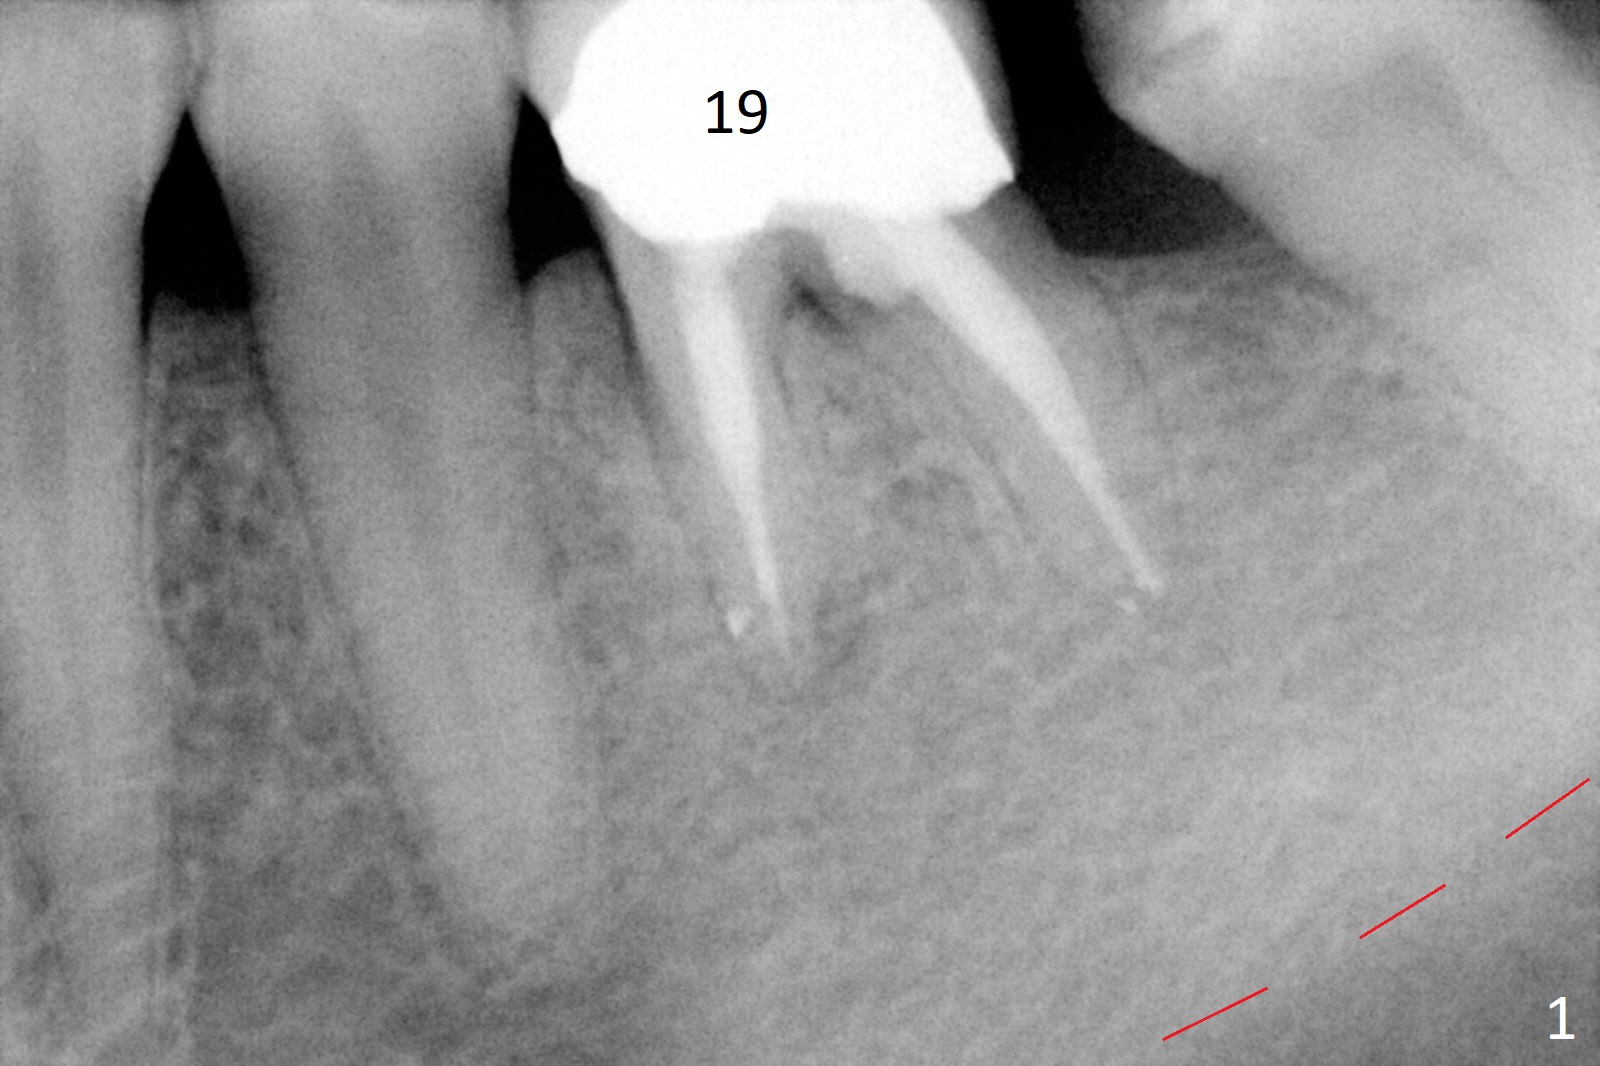

A 50-year-old man will return for #19 implant placement following the one at #30. In the last 9 years, the tooth have broken down with formation residual roots and loss of one of them (Fig.1,2). More important is the coronal portion of the alveolar bone becoming apparently thinner (Fig.2 *). There is also bone loss associated with the neighboring tooth (arrow). It is expected that the implant to be placed will be narrower and/or shorter than the one at #30. After removal of the distal residual root, use Magic Split as a scalpel to extend an incision mesially and start bone expansion, followed by Magic Expanders and IS drills if needed. Take preop photos to show the atrophic mesial ridge.